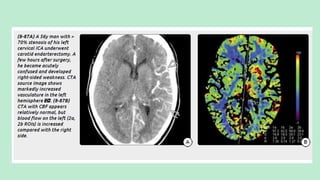

CEREBRAL HYPERPERFUSION SYNDROME:

Cerebral hyperperfusion syndrome (CHS) is a rare but potentially devastating

disorder.

CHS is sometimes called luxury perfusion or postcarotid

endarterectomy hyperperfusion and is defined as a major increase in

cerebral blood flow well above normal metabolic demands.

CHS most often occurs as a complication of carotid reperfusion procedures

(i.e., endarterectomy, angioplasty, stenting, or thrombolysis).

Critical carotid stenosis with chronic cerebral ischemia causes endothelial

dysfunction and impaired arterial autoregulation.

Loss of normal vasoconstriction results in chronic dilatation of the

brain "resistance" vessels.

When normal perfusion is restored, this can result in rapidly increased

cerebral blood flow (CBF) in the previously underperfused hemisphere.

Patients typically present within a few hours following carotid

endarterectomy (CEA), usually with unilateral headache, face or eye pain,

cognitive impairment, and variable neurologic deficits.

IMAGING

NECT scan: May show only mild gyral swelling.

CTA/pCT: Show congested, dilated vessels with elevated blood flow and

decreased MTT/TTP

MR Findings:T2/FLAIR scans show gyral swelling, hyperintensity, and

sulcal effacement in the internal carotid distribution.

T1 C+ scans may be normal or show mildly increased intravascular

enhancement.

DWI is typically negative, as the edema is vasogenic rather than cytotoxic.

pMR shows elevated CBF and cerebral blood volume with decreased

(shortened) MTT.

Postprocedure CHS on TOF-MRA is seen as an increase in the

change ratio of signal intensity more than 1.5x the preoperative level.

Nuclear Medicine: Single-photon emission computed tomography

(SPECT) has demonstrated focal hyperperfusion at the

revascularization